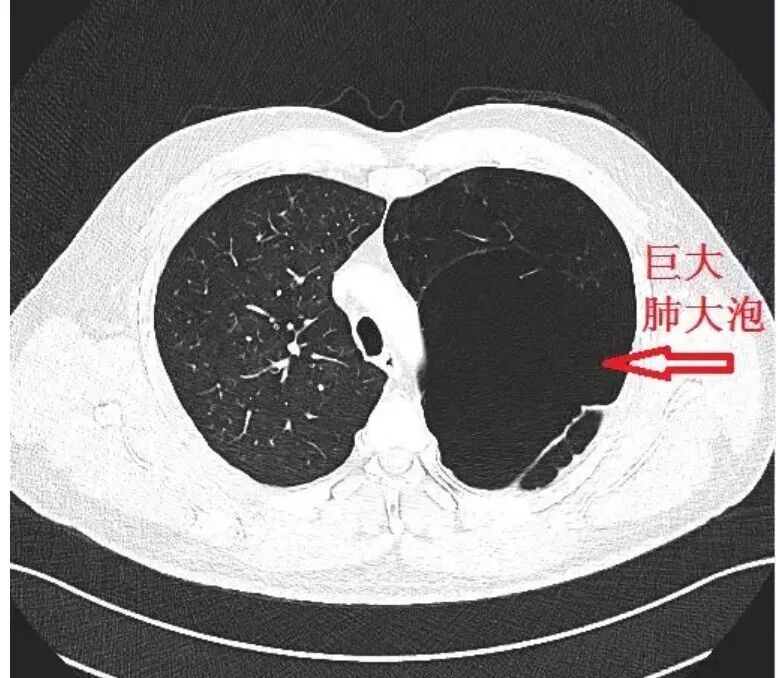

巨大肺大泡.png